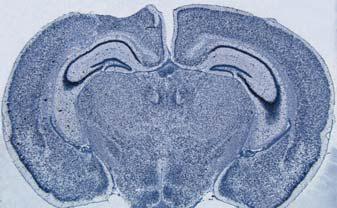

新一代的徠卡數(shù)字顯微鏡,用于生物醫(yī)學(xué)研究領(lǐng)域。

**眼感覺該顯微鏡的設(shè)計(jì)簡潔美觀。通過**次仔細(xì)觀察,發(fā)現(xiàn)它具有引人入勝的洞悉力。徠卡數(shù)字顯微鏡系列。該類顯微鏡具有**的圖像清晰度和圖像對(duì)比度--- Leica研究生物顯微鏡DM4000 B**Leica研究生物顯微鏡DM6000 B用于生命科學(xué)和**研究。